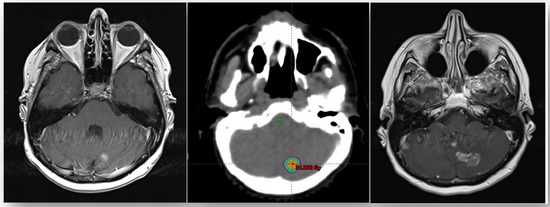

| Brain fSRT | 32 | 100 |

| PTV | ||

| Median | 2.26 cm3 | |

| Range | 0.8–54.4 | |

| Brain Metastases Location | ||

| Parietal lobes | 5/32 | 15.6 |

| Frontal lobes | 7/32 | 21.9 |

| Occipital lobes | 2/32 | 6.3 |

| Temporal lobes | 8/32 | 25.0 |

| Cerebellum | 5/32 | 15.6 |

| Brainstem | 5/32 | 15.6 |

| Total dose | ||

| Median | 27 | - |

| Range | 12–27 | |

| Dose per fraction | ||

| Median | 9 | |

| Range | 4–9 | |